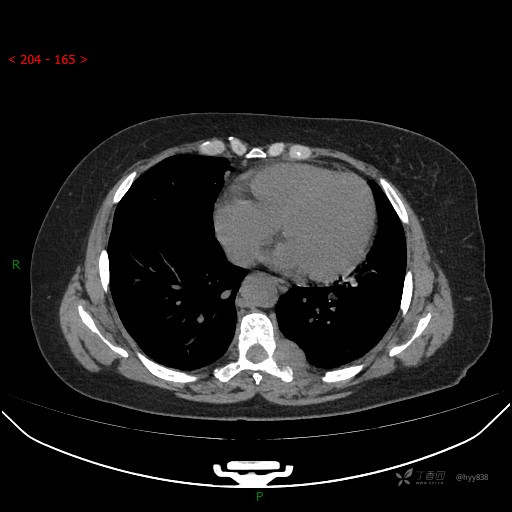

增强